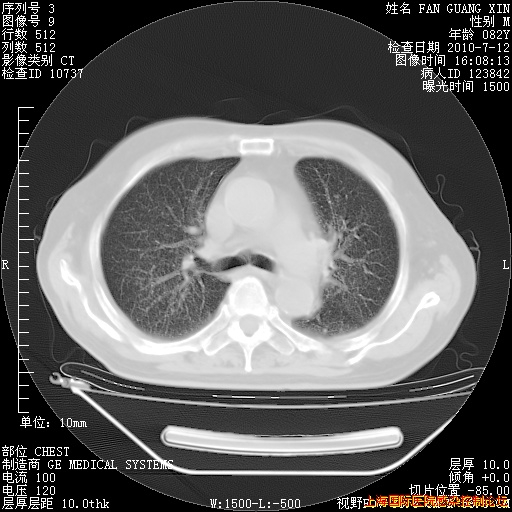

6月12日肺窗

今天复查CT